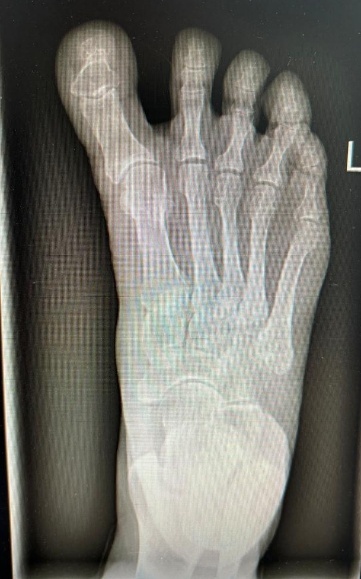

Radiographic evaluation demonstrated effective correction of the hallux alignment. The mean hallux valgus angle (HVA), which was negative in all cases preoperatively (mean –16.5° ± 4.2), improved significantly to a postoperative mean of 5.7° ± 3.2 (p = .0156), with all patients achieving alignment within the physiologic range. Representative radiographs are presented in Figures 1 and 2.

The intermetatarsal angle (IMA) remained stable, changing minimally from a preoperative mean of 3.9° ± 1.6 to 3.7° ± 1.4 postoperatively (p = .6547), suggesting that the procedure achieved targeted realignment of the great toe without affecting the overall first-ray geometry.